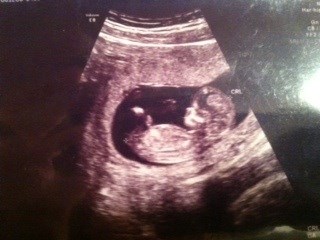

Efter en skøn nf scanning igår, er jeg blevet flyttet 2 dage, hvilket nu betyder termin d 30 juni

Vedhæftede fotos (klik for at se i fuld størrelse)